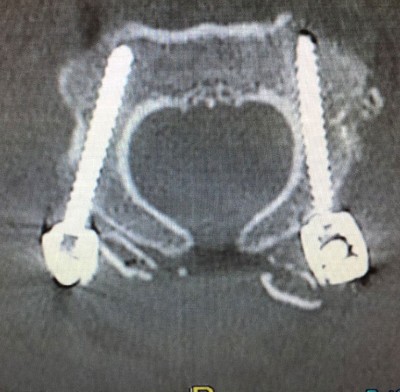

In the Axis, pedicle screws are usually the first choice although, depending on the patient’s anatomy, placement of isthmic screws may be considered. Atlas’ screws are generally placed in the lateral masses. Atlas and axis screws are joined in each side by lateral bars that are unifying the instrumented fusion system. In most cases it is convenient to put bone graft, usually autologous, taken from the iliac crest or the patient’s own rib. In the cases where it is not possible to obtain autologous bone graft, heterologous graft (artificial bone) may also be used.

After the preoperative analysis of the Magnetic Resonance Imaging (MRI) and CT scan of each patient, we perform a thin sliced preoperative CT oriented towards neuronavigation that will be carried out during surgery. Prior to surgery we perform a surgical planning of the intraoperative neuronavigation to confirm the trajectories of screws and special anatomical dispositions of structures. It is also important to know and evaluate patients’ concomitant diseases or comorbidities which are frequent in patients affected by Ehler Danlos, such as POTS, Mast Activation Syndrome, cardiac abnormalities … etc. Knowing this it allows to anticipate any possible problems in the postoperative period.

Once in the Operating Room, surgery is performed under general anesthesia, with Neurophysiological monitoring (SSEP – somatosensory evoked potentials), neuronavigation guidance and intraoperative fluoroscopy guidance. Thus we control the spinal cord and nerves (cranial and cervical) in order to avoid potential damages to these important structures. Neuronavigation assistance guides us all through the surgery, thus it diminishes (though it does not eliminate) the risks while placing the screws for the fusion. Both neurophysiological monitoring and neuronavigation guidance are safety measures for the patient.